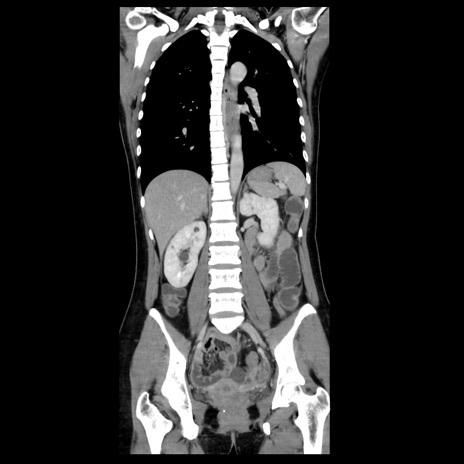

症例39(冠状断像)

【症例】40歳代女性

【主訴】上下腹部痛

【現病歴】2日目から下腹部痛あり。夜間は痛みで眠れなかった。昨日より上腹部痛と下痢が出現。臥位で痛みは軽快したため、休んでいた。本日になって臥位でも立位でも痛みが強くなってきたため救急要請。

【既往歴】子宮内膜症

【身体所見】部:平坦・軟、左上下腹部に圧痛あり、反跳痛あり。

【データ】WBC 21800、CRP 26.78

CT